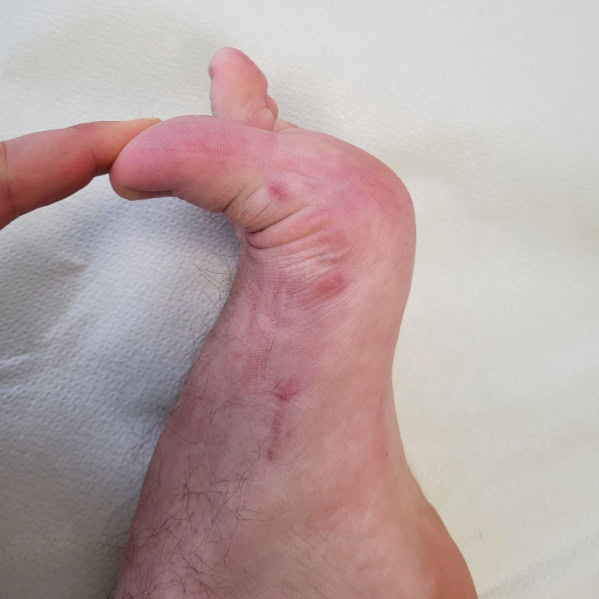

Objawy palucha koślawego są zazwyczaj jednoznaczne i trudne do przeoczenia. Najczęściej obejmują:

- widoczne, boczne odchylenie palucha i zaburzenie jego osi,

- bolesny guz przyśrodkowy w okolicy głowy I kości śródstopia; często objęty stanem zapalnym (zaczerwienienie, obrzęk kaletki),

- trudności w doborze obuwia i jego noszeniu, na późniejszym etapie ograniczenie aktywności fizycznej,

- zmiany towarzyszące – palce młotkowate, modzele podeszwowe i metatarsalgia.